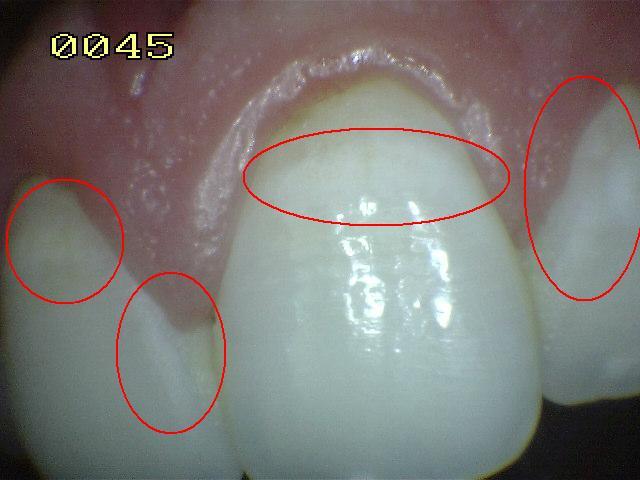

Código 2

(Caries Inicial): Lesión de

caries observada en esmalte en estado húmedo y permanece después de secar

- Cuando la superficie de esmalte se

observa en estado húmedo hay un cambio de color

(mancha blanca o marrón) y después del secado con aire

por 5 segundos se visualiza los rasgos típicos

de la (mancha blanca

/ marrón). Estas lesiones se encuentran tocando el

margen gingival o a un milímetro de este.